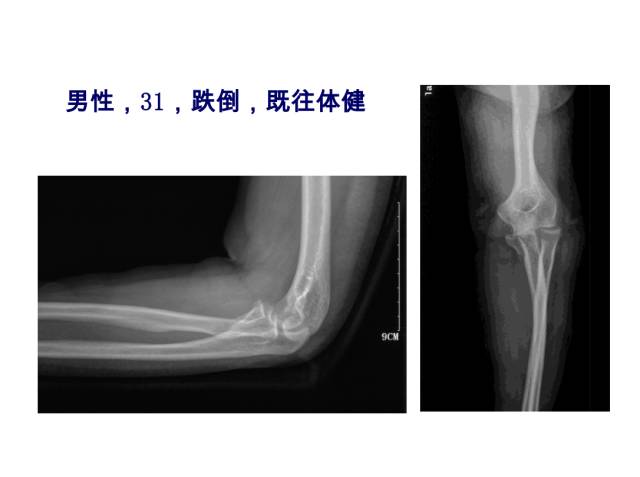

冠突是一个非常重要的稳定结构

• Ⅰ型和Ⅱ型单纯冠状突骨折,发生后方半脱位的风险很小,允许早期活动

• 即使单纯Ⅲ型骨折,在很小的生理应力下也有可能发生后方半脱位,特别是在屈肘60°~105°,支持对Ⅲ型损伤ORIF